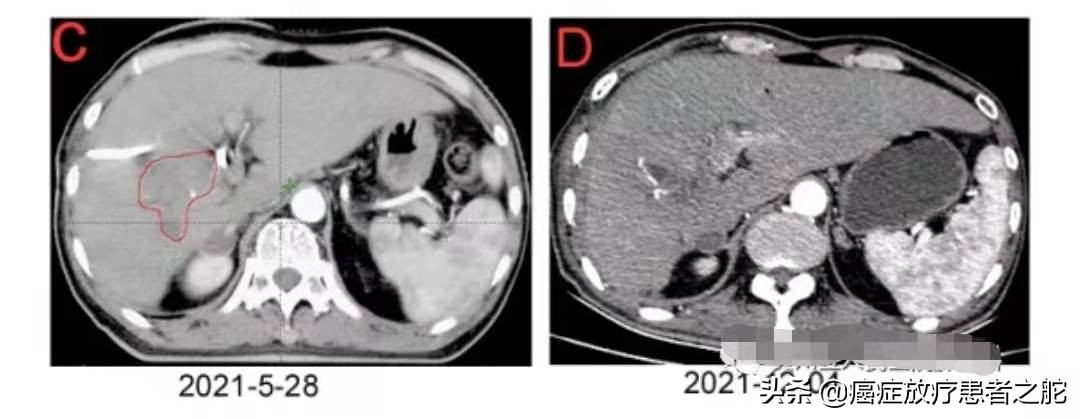

近期患者到医院复查,肺内转移病灶,放疗后彻底消失。而且,去年上半年,肝脏复发区域,也进行了放疗干预,这次复查,提示效果也很不错。具体如下图所示:

患者看到自己的复查结果,感慨万千,十分开心,抗癌信心大增。 或许,他还将创造更多的别人认为的不可能。